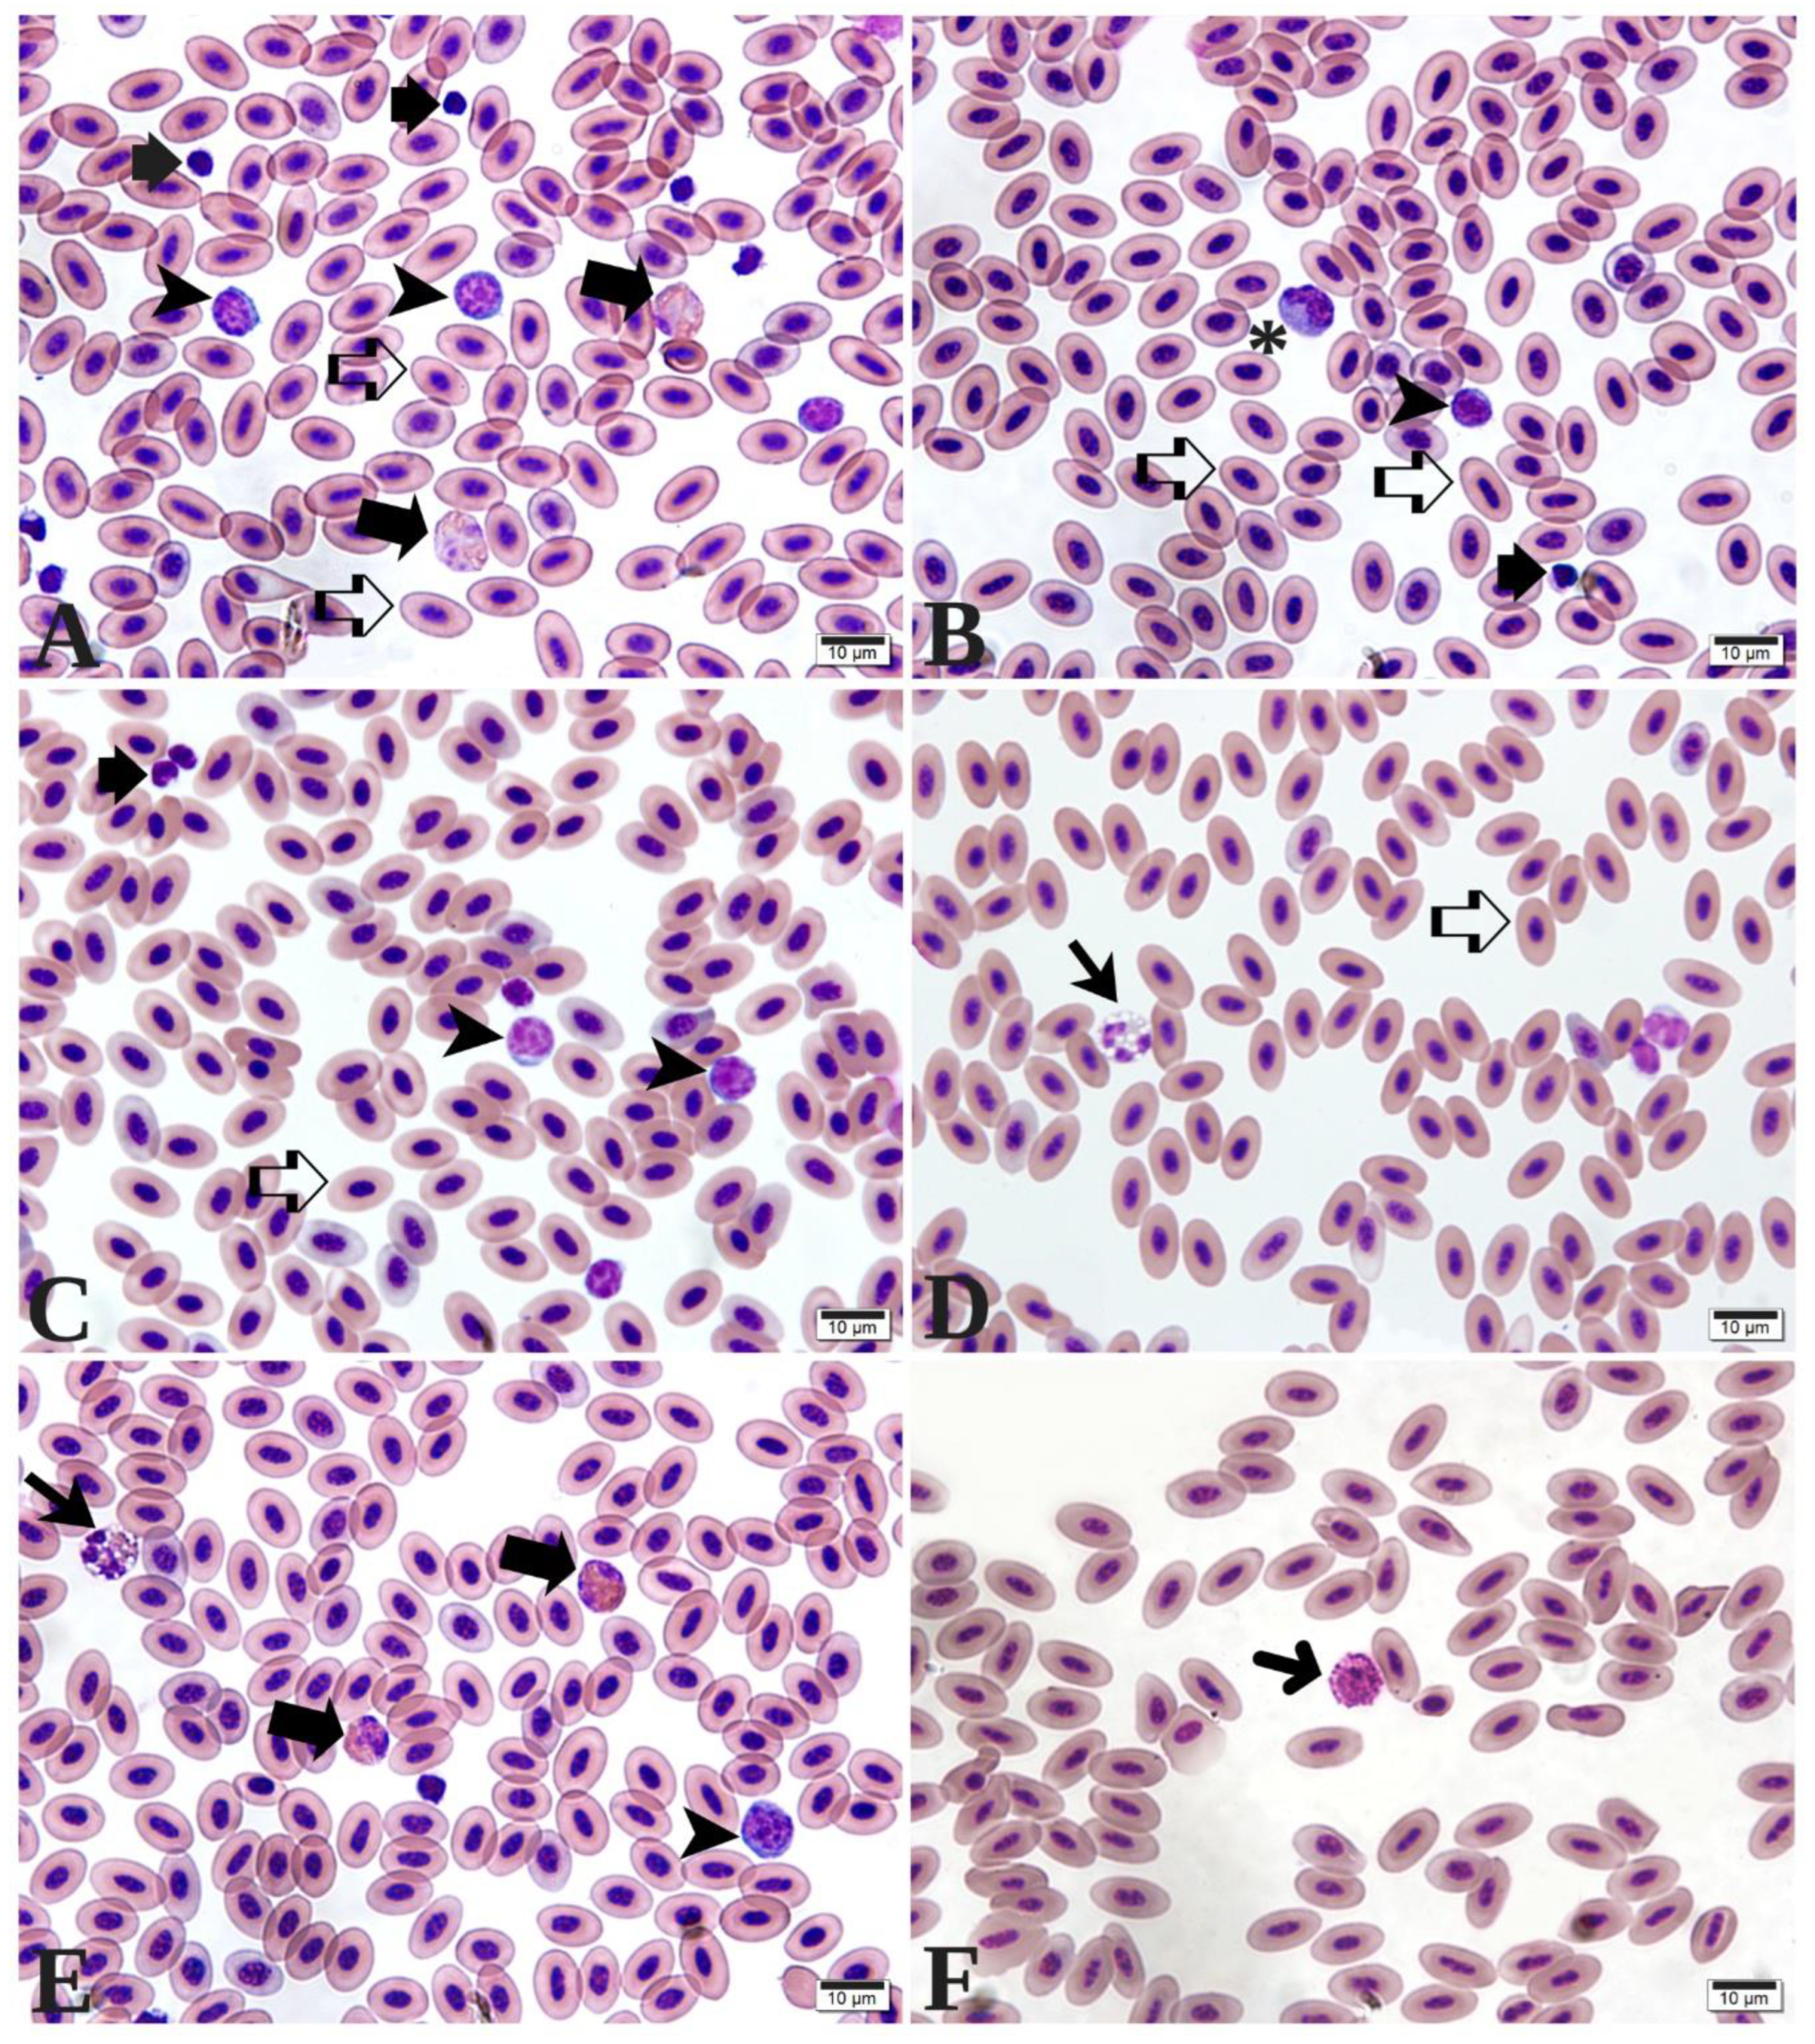

3.1. Hematological Parameters